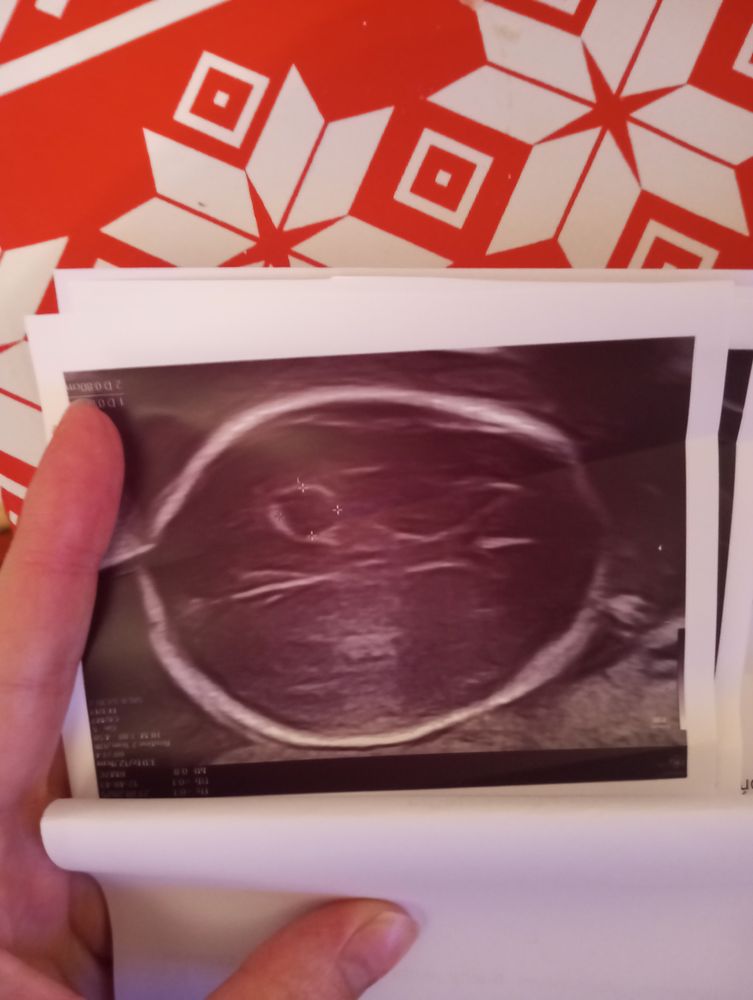

Киста в голове у ребенка

Анализы, скринингиДевочки привет.На втором скрининге на сроке 20,5 обнаружили кисту с жидкостью в левой части желудочка головного мозга размером 7*8 мм.Скажите у кого так же было?С чем это связано и ушло ли это образование?